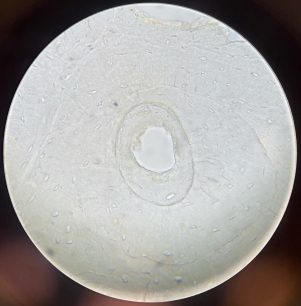

Muscular Arteries (Medium Sized Arteries)

Muscular Arteries (Medium Sized Arteries)

Muscular Arteries (Medium Sized Arteries)

Elastic Arteries (Aorta)

Elastic Arteries (Aorta)

Elastic Arteries (Aorta)

Lymphatic Vessel

Lymphatic Vessel

Lymphatic Vessel

Lymphatic Vessel

Lymphatic Vessel